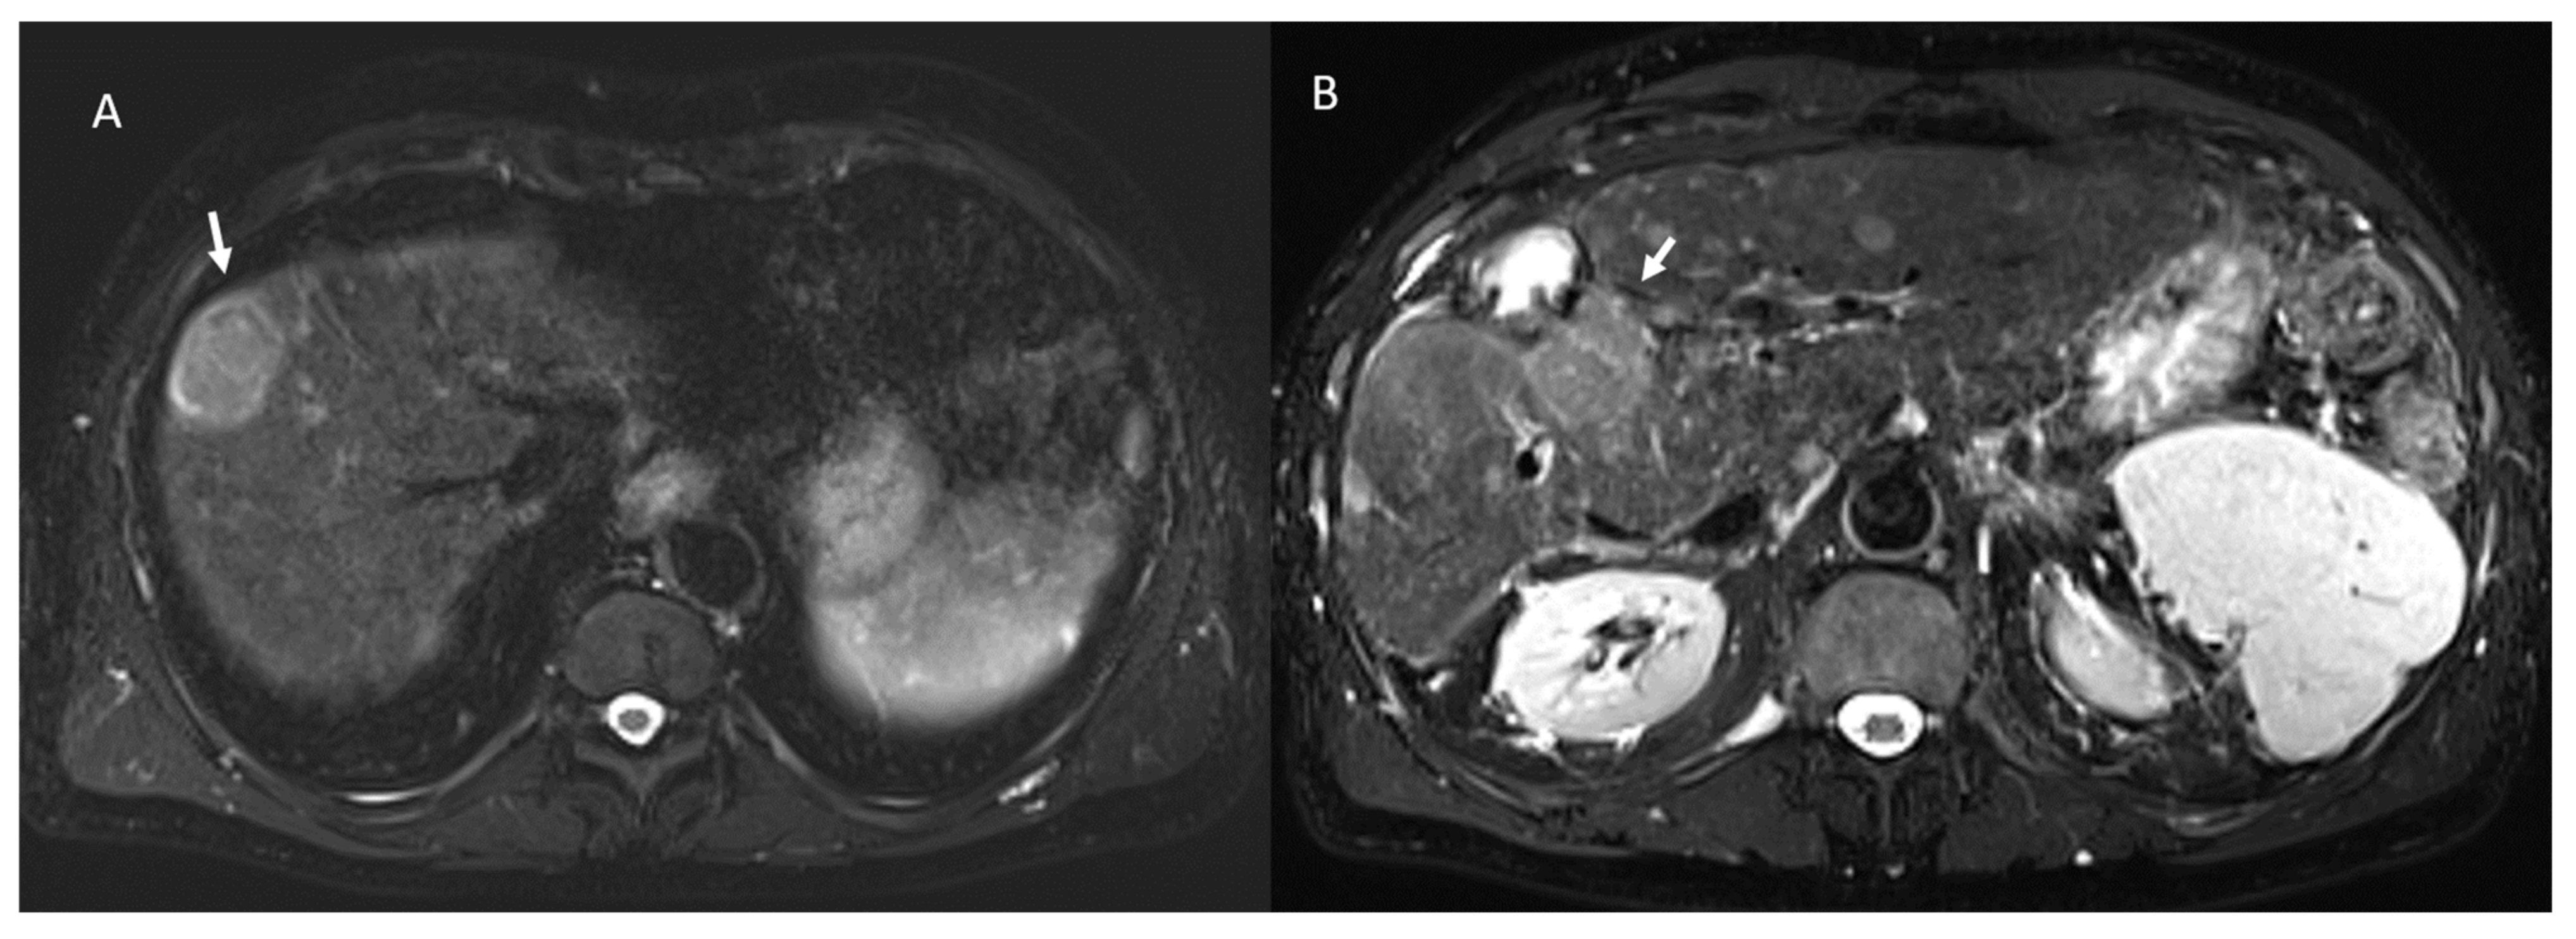

- 23 lesions were hyperintense in T2-W and hypointense in T1-W sequences (Figure 3).

- 98 showed iso-hypointense SI in T2-W and 15 iso-hyperintense SI in T2-W (Figure 6).

- 100 showed hyperintense SI in T1-W and 113 targetoid appearance.